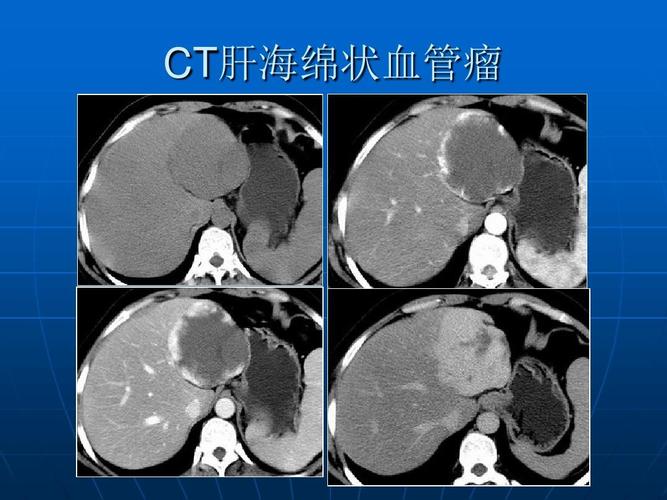

ct肝海绵状血管瘤

肝血管瘤ct

肝血管瘤图片